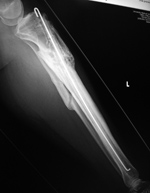

Intramedullary tibial nail and fibula Rush rod

43 year-old man with complex, healing right tibia and fibular fractures. There is an intramedullary rod (nail) in the right tibia. Four locking screws are present proximally and two distally. After dynamization the distal locking screws have been removed.

Intramedullary tibial nail with lower extremity wound vac (arrow)

Tibial intramedullary nail and wound vac